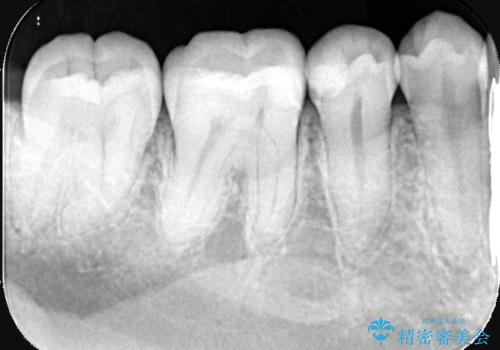

- 主訴:右下の奥歯がたまに冷たい物や甘いものでしみる

右下6番目の歯に大きめのう蝕を認め、形態の再現性を考えインレーでの治療となりました。

右下6の近心にう蝕が認められう蝕の範囲が大きかったため、歯冠形態の再現性の高いインレーでの修復とし、材質は審美性、清掃性に優れたセラミックを選択しました。